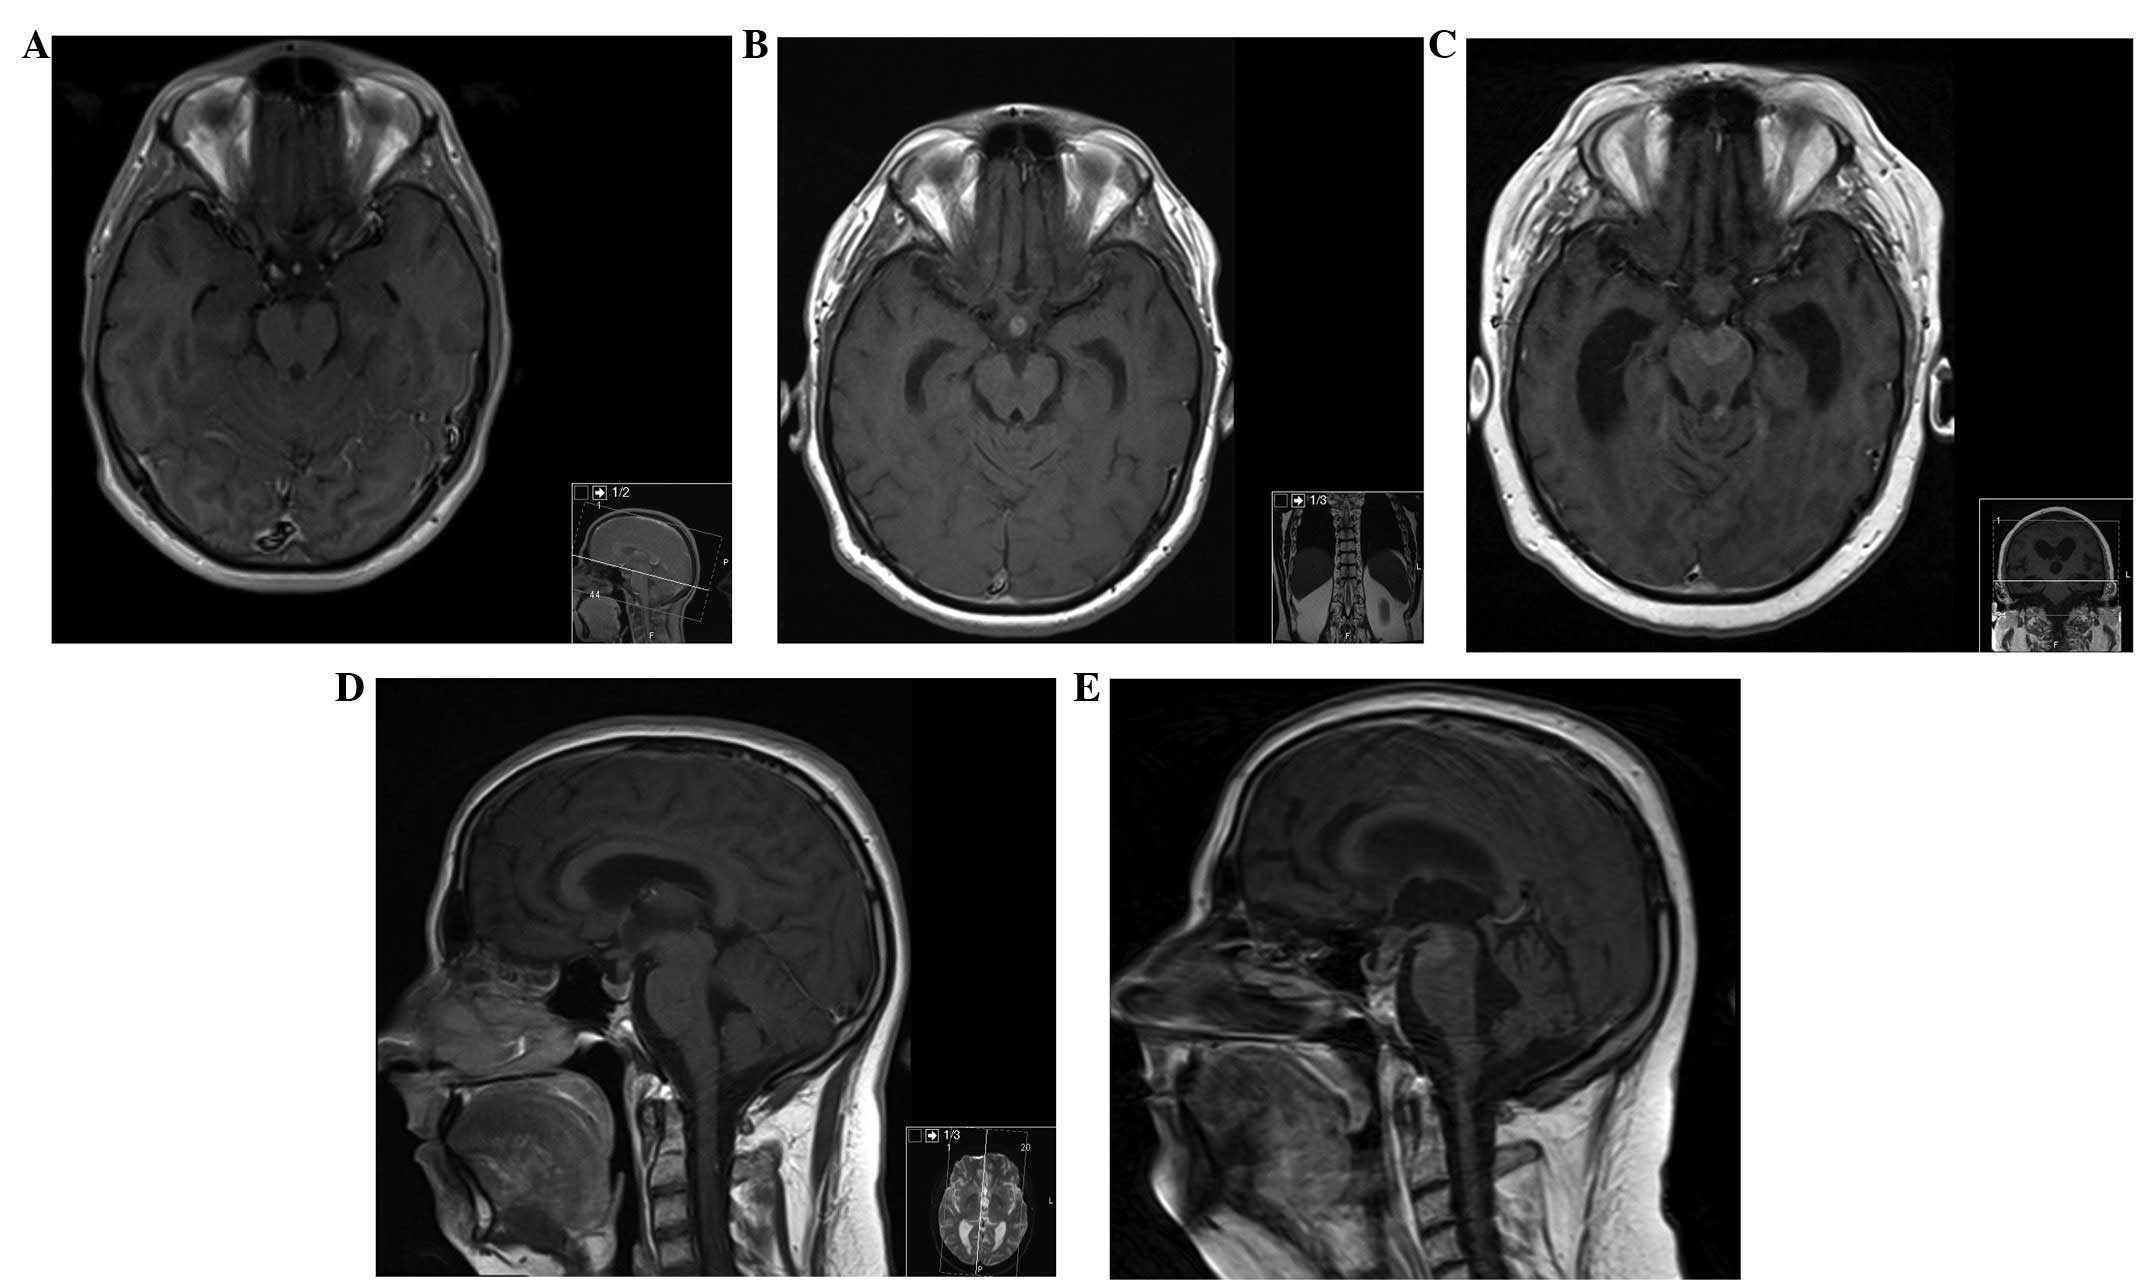

Figure 3

MRI of the brain. (A) Axial section, contrast-enhanced T1-weighted MRI of the brain, at presentation, demonstrating no lesions. (B and D) Axial and sagittal section, respectively, contrast-enhanced T1-weighted MRI of the brain, at 6 months after initial presentation, showing a metastatic deposit in the pituitary stalk. (C) Axial and (E) sagittal section contrast-enhanced T1-weighted MRI of the brain, at 17 months after initial presentation, demonstrating new metastatic deposits in the interpeduncular cistern and in the left superior cerebellar peduncle. MRI, magnetic resonance imaging.

Neuroaxis MRI performed 17 months after surgery revealed an enlargement of the enhancement mass from T3 to T12 with less perilesional oedema and a new metastatic deposit in the interpeduncular cistern and left superior cerebellar peduncle.

Serial MRI at 3, 6 and 17 months was performed (Fig. 3). Six months after surgery the patient deteriorated, becoming completely paraplegic and losing bladder function. Cranial and spine MRI revealed enlargement of the residual tumour from T3 to T12 with cranial extension of oedema to the obex, and subarachnoid metastatic deposits in C2, C4 and in the pituitary stalk, with hydrocephalus. We proposed cranio-spinal irradiation, but as the patient was stable and without signs or symptoms of increased intracranial pressure (ICP) the patient and his family decided to withhold this treatment and wait.